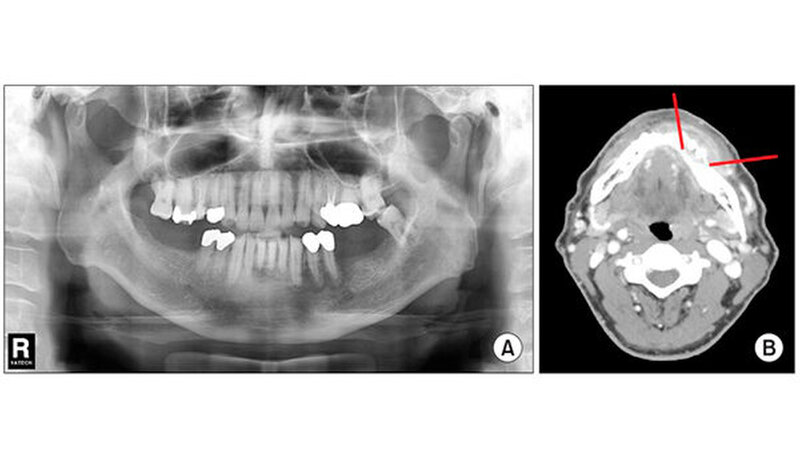

Die Zahnärzte fanden heraus, dass die Entzündung von den Zähnen herrührte. Sie diagnostizierten eine linke Unterkiefer-Osteonekrose infolge einer Gürtelrose des Gesichtsnervs (Nervus trigeminus. Abgestorbene Knochen- und Zahnfragmente (Sequester) wurden entfernt, die Zähne 31 bis 35 extrahiert (Abb. 3).

Die intraorale Untersuchung zeigte einen freiliegenden Alveolarknochen in den Bereichen 34, 35 sowie eine Lockerung dritten Grades der Zähne 31 bis 35. (Abb. 1 B) Röntgenaufnahmen offenbarten eine diffuse und unregelmäßige strahlendurchlässige Knochenläsion im linken Unterkiefer sowie eine Weichteilschwellung mit niedriger Dichte. (Abb. 2) Mithilfe einer Biopsie stellten die Zahnärzte akute und chronische Entzündungen fest. Der Patient hatte weder Rezepte für Medikamente verschrieben bekommen, die den Knochenstoffwechsel beeinflussen, noch hatte er jemals eine Strahlentherapie erhalten.